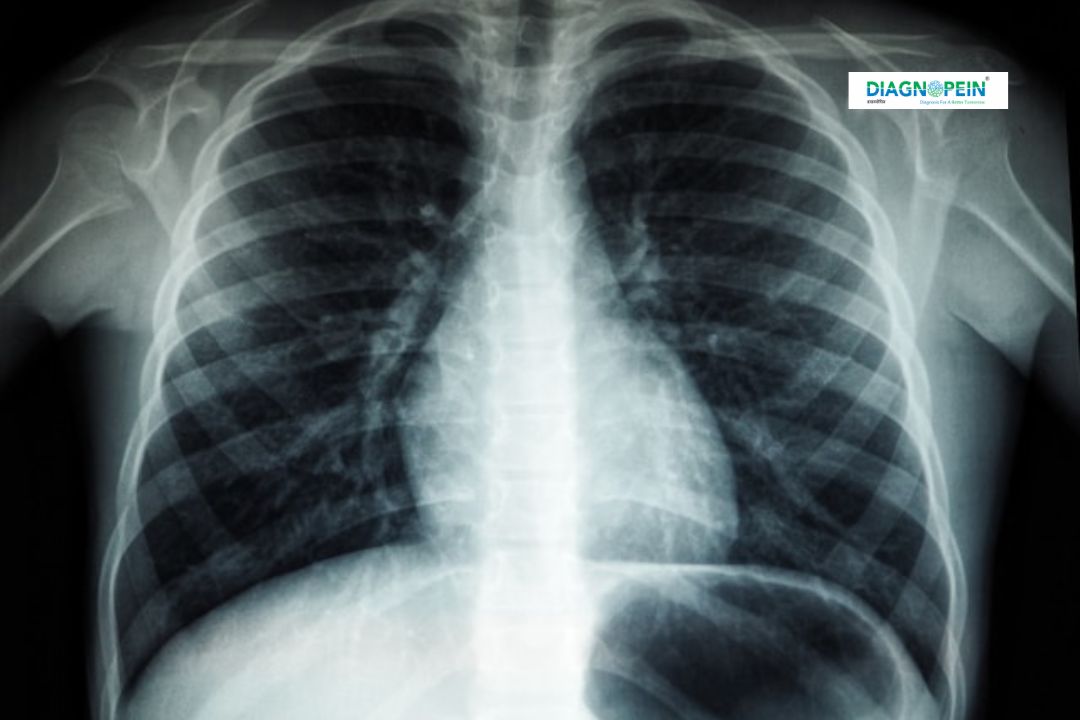

Diagnopein offers advanced X-Ray Chest PA/LAT imaging in Karad to help doctors assess the condition of the lungs, heart, and chest cavity. The PA (Posteroanterior) and LAT (Lateral) views are the standard imaging positions that provide comprehensive visualization of chest structures. Using modern digital radiography, our scans ensure detailed, high-resolution images that assist in accurate diagnosis and effective treatment.

An X-Ray Chest PA/LAT is one of the most commonly recommended diagnostic tests for identifying respiratory diseases, infections, fractures, or abnormalities in the chest region. At Diagnopein, every examination is conducted by trained technicians under expert radiologist supervision, ensuring the best quality results in minimal time.

A radiologist carefully analyses several parameters on the X-Ray Chest PA/LAT, including:

1. Lung clarity and structure

2. Heart size and shape

3. Diaphragm position and movement

4. Rib and bone alignment

5. Air or fluid in pleural spaces

These insights allow for early identification of diseases, guiding further treatment or investigations like CT scans, if required.